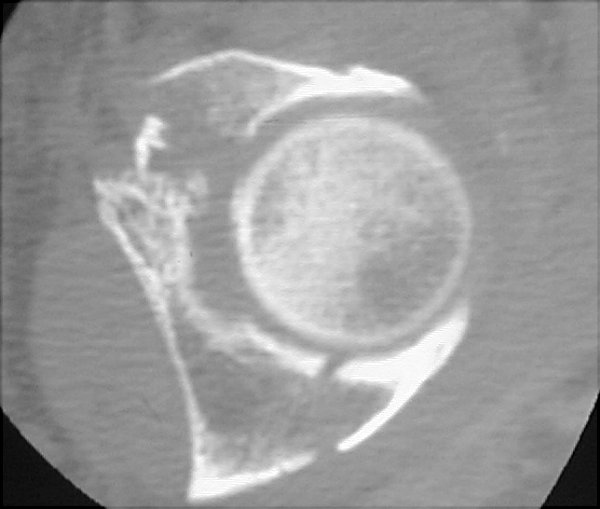

Return to Dashboard Fracture